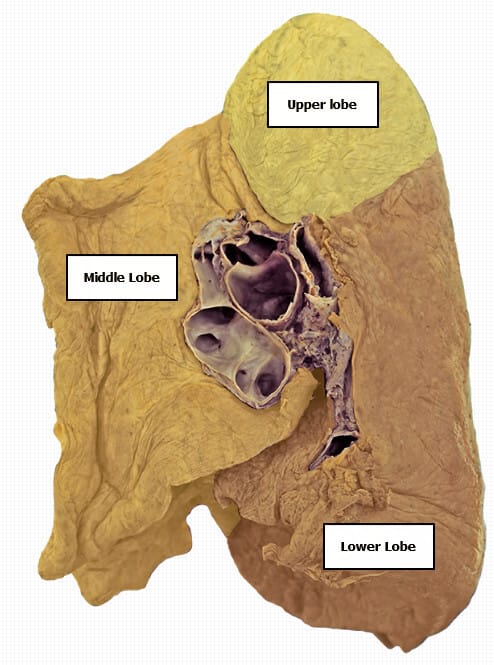

Right Lung

- Upper lobe

- Middle lobe

- Lower lobe

Right Lung – Medial Aspect